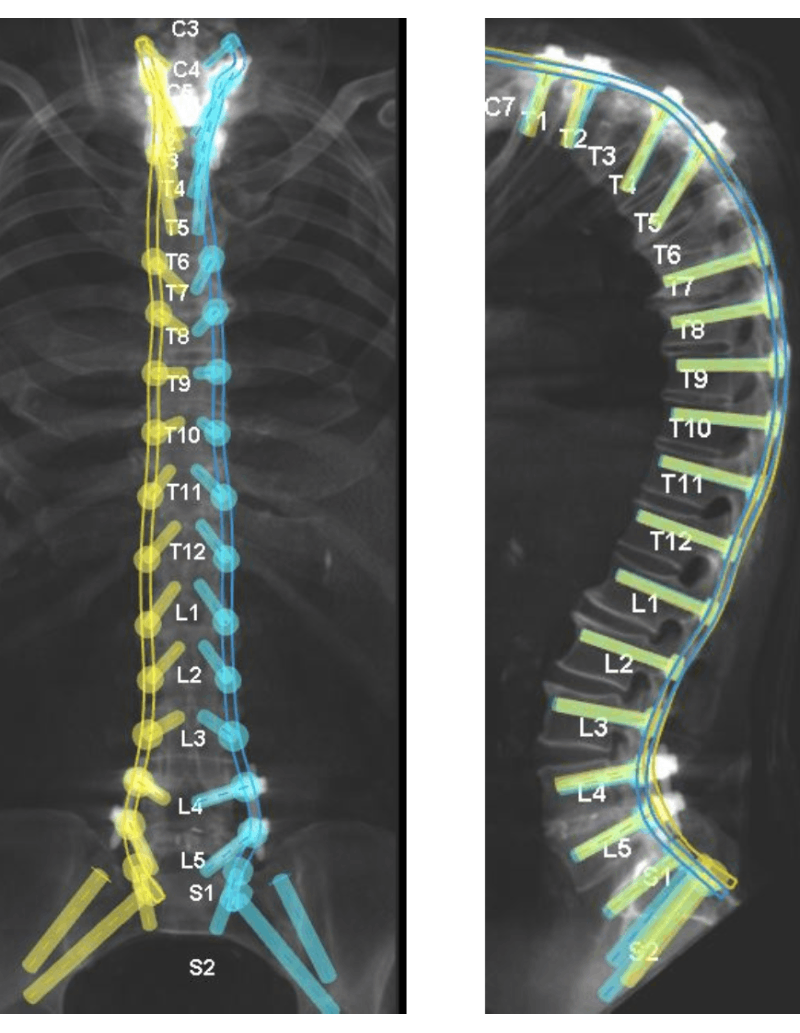

Post op x-ray of patient's spine

Post-operative lateral X-ray showing improvement of the thoracic spine hyperkyphosis and the upright posture of the cervical spine.